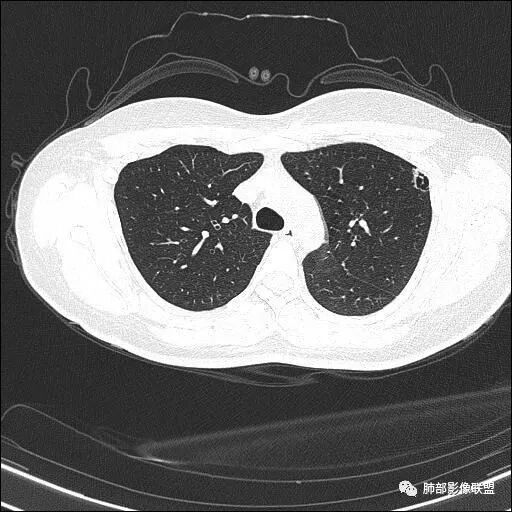

双肺上叶多发结节影及纤维索条影,部分结节内部可见空洞形成,形态欠规则,洞壁厚薄均匀,以胸膜下分布为主,多灶性,多态性,临床年轻女性,体检发现,考虑结核,寄生虫?NTM.

双肺上叶尖段分布为主多发囊腔伴斑点,斑片影,囊腔壁不规则,部分内见分隔。考虑结核可能

两肺多发囊或空洞(部分腔内不干净可见间隔影)+多发结节 (右侧胸膜下的结节显著)+左肺尖斑片影。年轻女性,体检发现。考虑结核?鉴别PLCH(奇异囊加结节,吸烟男性多见),转移瘤(要有原发肿瘤病史)

双肺上叶多发结节影,形态不规则,部分结节内部可见空洞形成,洞壁薄,胸膜下分布为主,年轻女性,体检发现,考虑结核

2.双肺多发薄壁空洞影、条索影及结节影,边界较清楚,密度偏高不柔和,散乱,但有成簇倾向或堆积感,胸膜下分布为主,双肺上叶分布为主。

3.空洞相当不规则,缺乏张力,未见血管穿行,未见壁结节,未见液平。

4.双肺门及纵隔未见肿大淋巴结。未见胸腔积液。